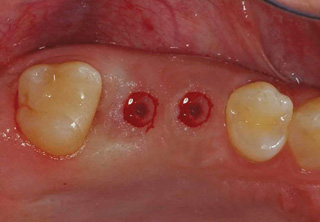

흔히 "네비게이션 임플란트"라고 말하는 컴퓨터 분석을 이용한 임플란트란?

컴퓨터 분석을 이용한 임플란트는 3차원 영상 분석을 통하여 적절한

임플란트의 식립 위치와 방향 등을 결정하여 치료계획을 수립하고,

이를 토대로 개별 맞춤 수술유도장치를 제작하여 시술하는 방법입니다.

일반적으로 잇몸을 절개하지 않고 시술하여 수술시간이 짧으며, 수술 후 통증이나 붓기, 출혈이 적은 장점이 있습니다.

3D 모의시술로 식립

시술 전 3D영상장치 등을 통한 진단계획과

모의 수술을 통해 환자의 골조직과 신경관의

위치 등을 파악하여 명확한 치료 계획을

수립하고 개별 맞춤 수술유도장치를

사용하므로 신경 손상 및 부정확한 임플란트

시술의 위험이 적습니다.

무절개 시술로 빠른 회복

무절개 시술이므로 일반 절개 시술에 비해

붓기와 출혈이 적어 염증 및 감염의 위험이

낮고 빠른 회복이 가능합니다.